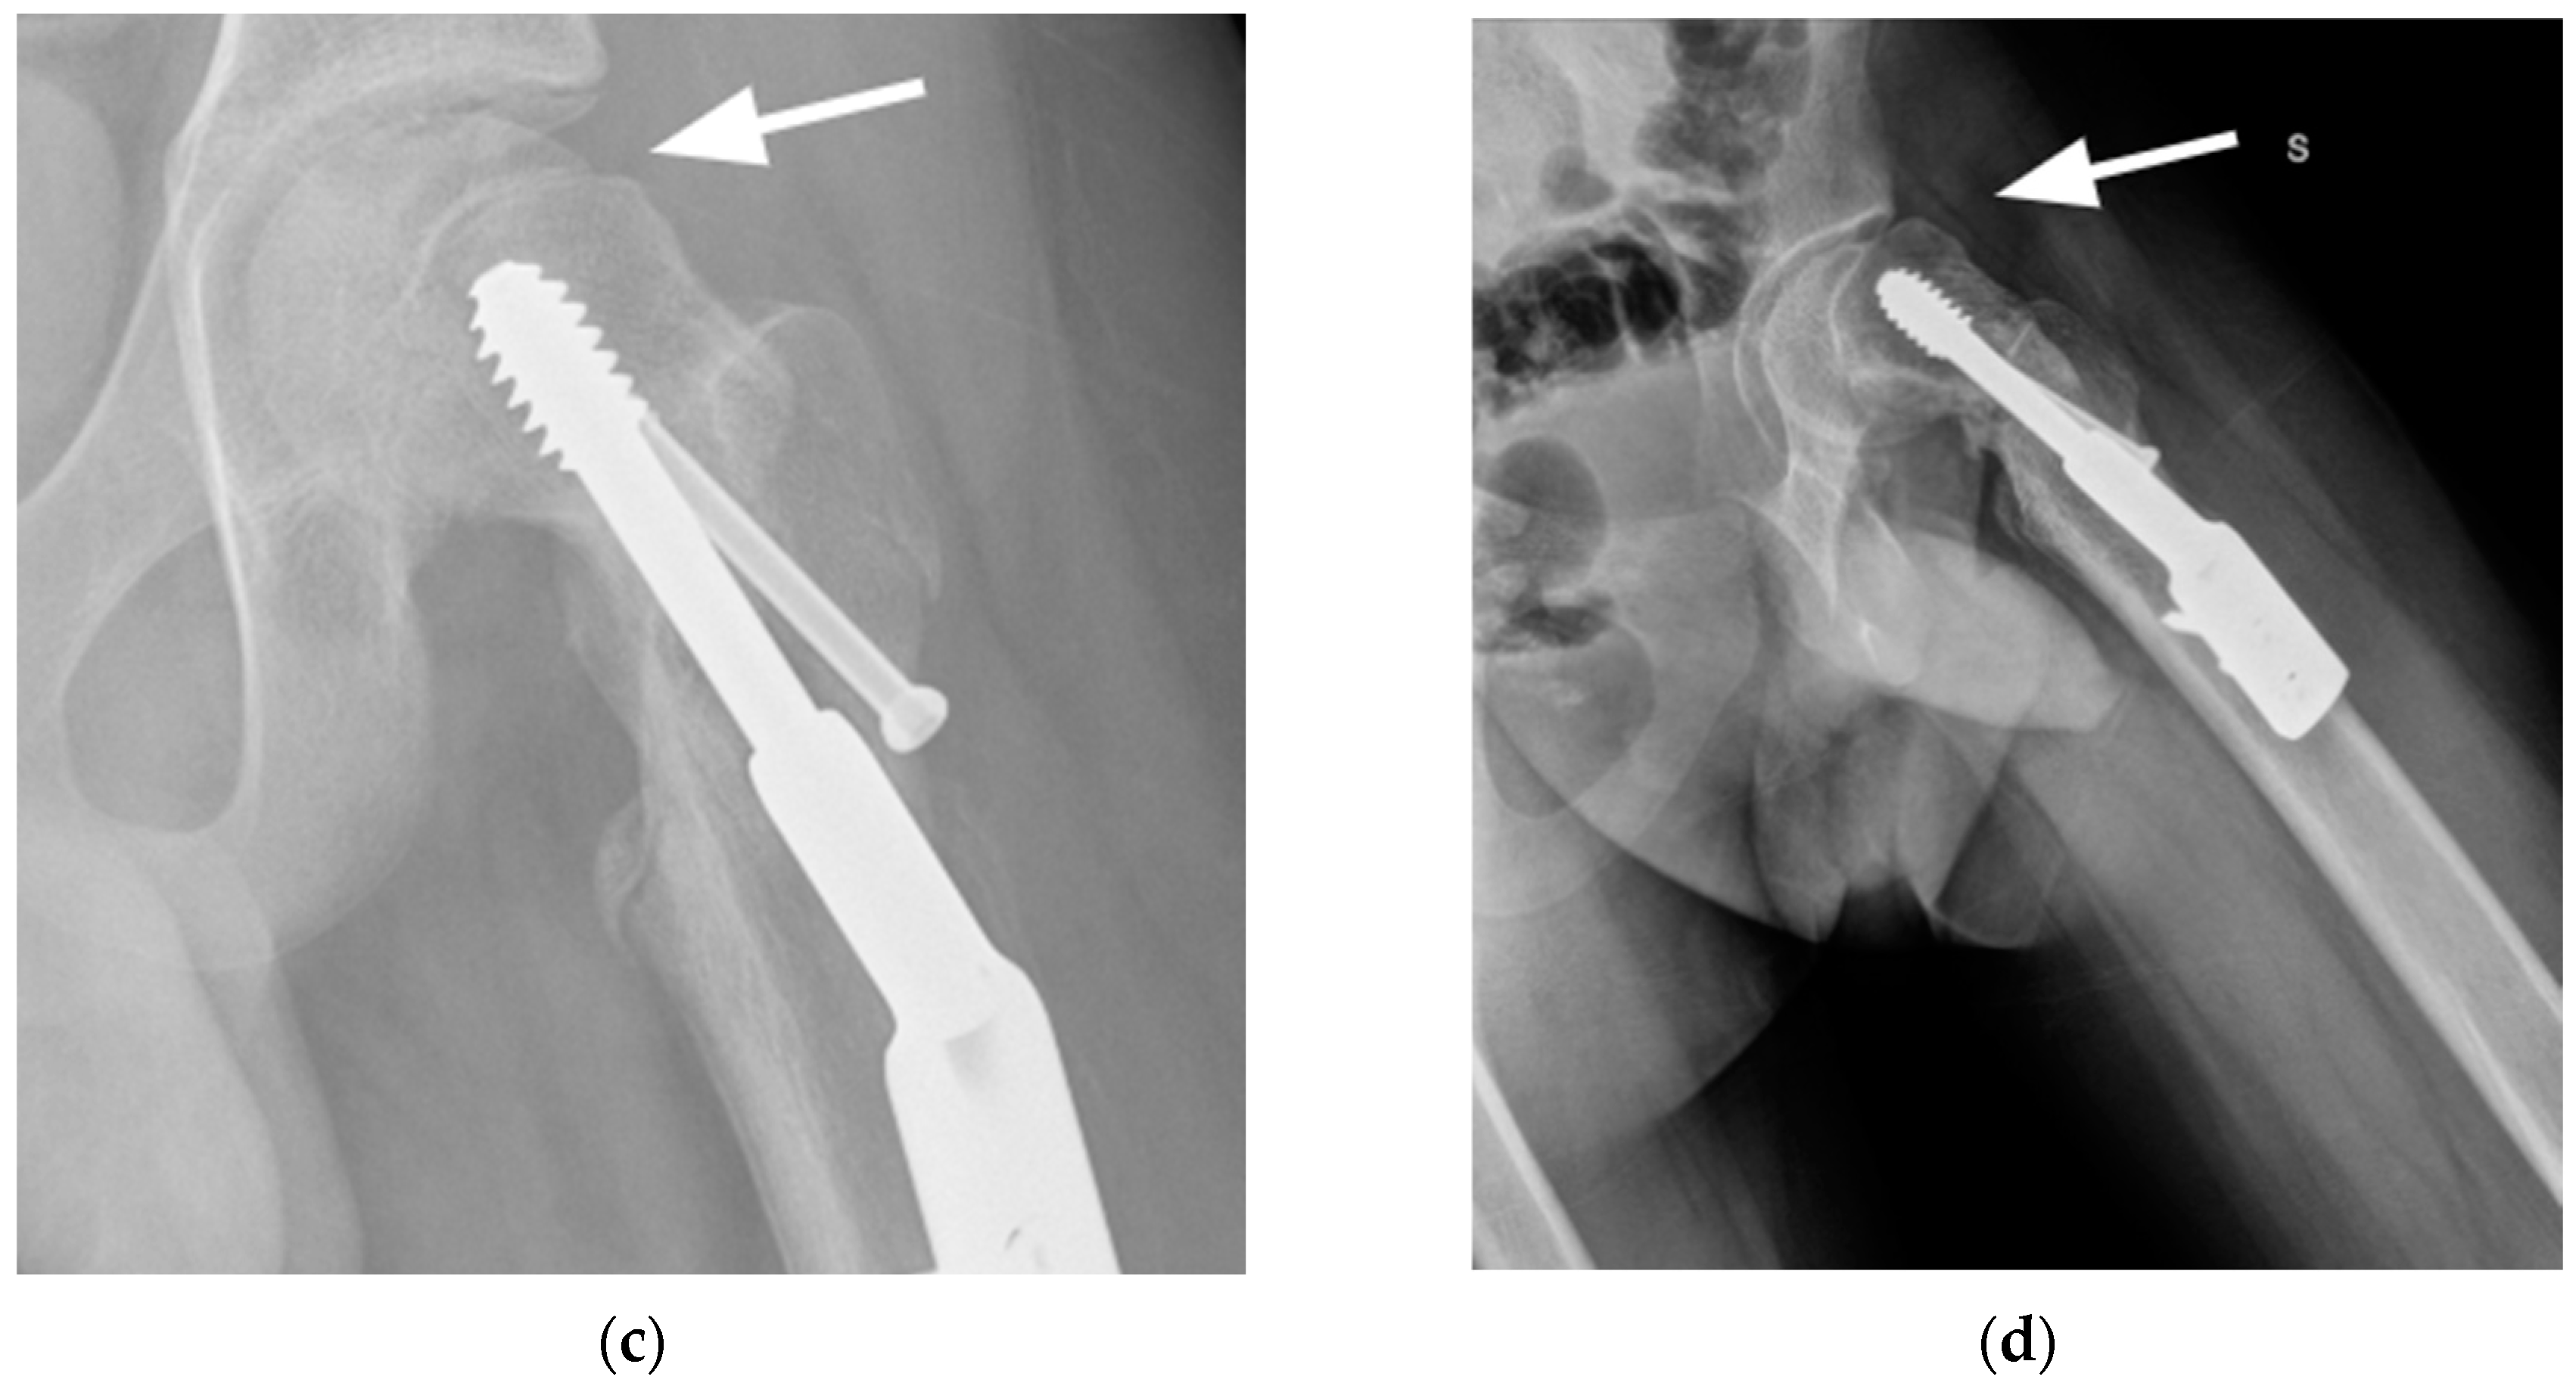

2.2. Surgical Procedure